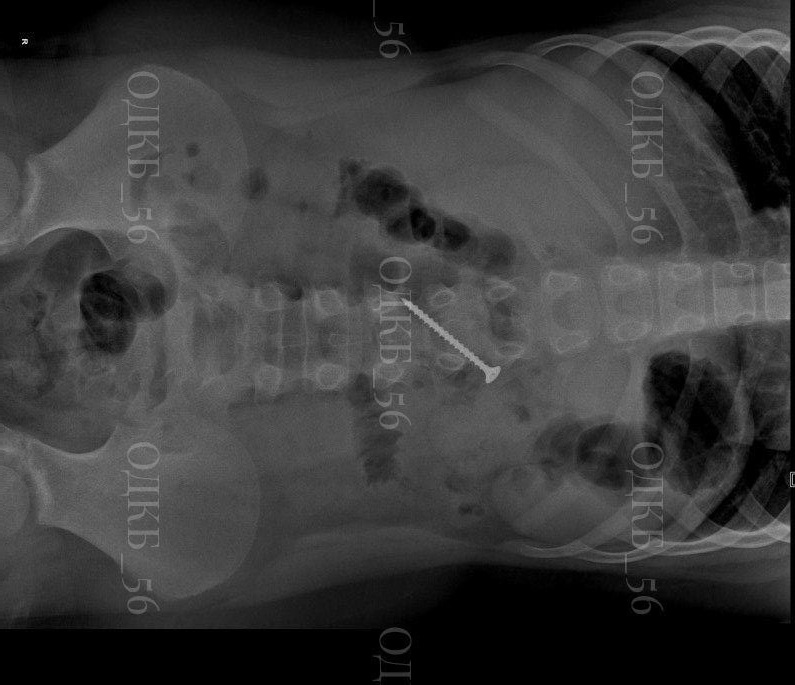

В Оренбурге врачи спасли 9-летнего школьника с саморезом в желудке

Мальчик дома случайно проглотил саморез. В приемное отделение ОДКБ он приехал уже с рентгеном брюшной полости из своей районной больницы.

За это время саморез успел оказаться в двенадцатиперстной кишке.

Ребенку грозила смертельная опасность. В любой момент кишечник мог проткнуть острый предмет, либо могла развиться кишечная непроходимость.

Врачи смогли оперативно удалить саморез с помощью эндоскопа. Мальчишку уже выписали домой.